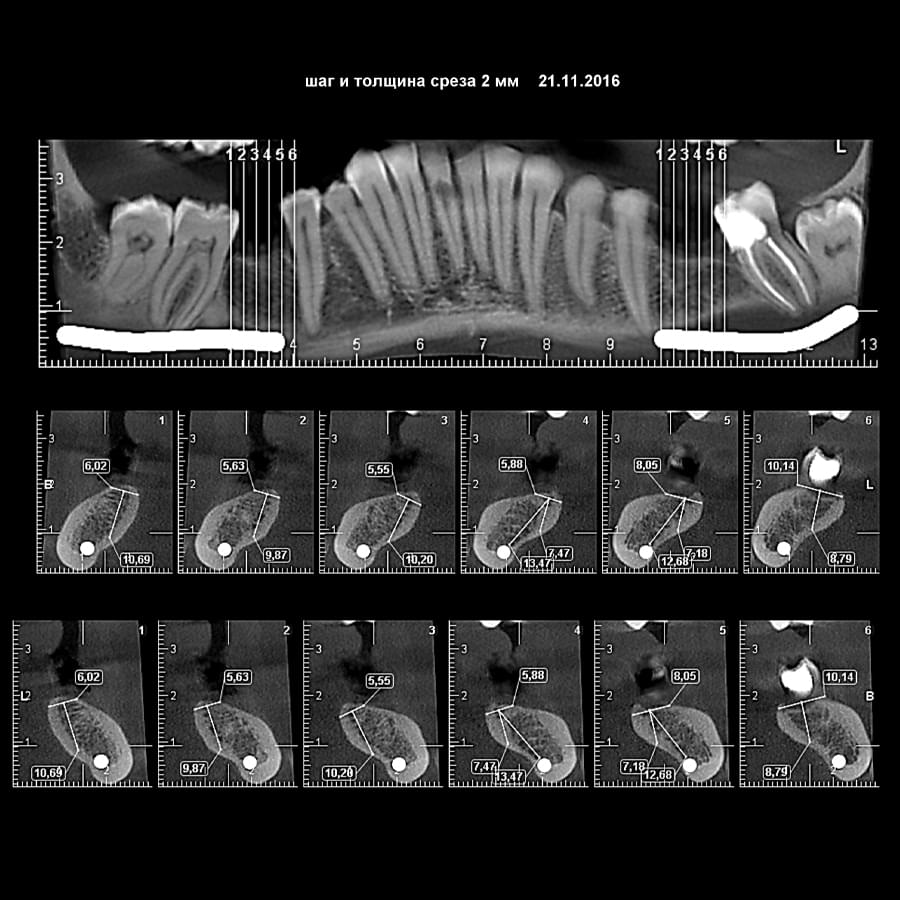

3D цефалометричний аналіз є сучасною технологією, яка дозволяє отримувати точніші,

комплексніші та надійніші дані про зубну та скелетну структуру. Ця технологія може стати

великим кроком в перед для ортодонтів, які хочуть забезпечити найкраще можливе лікування

своїх пацієнтів.

Основні переваги 3D цефалометричного аналізу:

Точність: 3D цефалометричний аналіз забезпечує точніше визначення розмірів та відстаней між

зубами та кістковими структурами.

Комплексність: ця технологія дозволяє отримувати детальні дані про різні структури, такі як

кістка та м'язи, що дозволяє ортодонтам докладніше досліджувати деякі патології та планувати

лікування.

Надійність: 3D цефалометричний аналіз дозволяє отримувати надійніші результати, оскільки

виключає можливість помилок, пов'язаних зі спотворенням або перекриттям зображень.